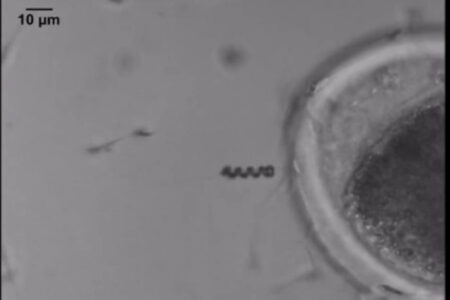

Indonesia Discover, JAKARTA — Para peneliti telah berhasil mengembangkan spermbot, sebuah teknologi robotik yang dirancang untuk menyerupai atau bekerja bersama…